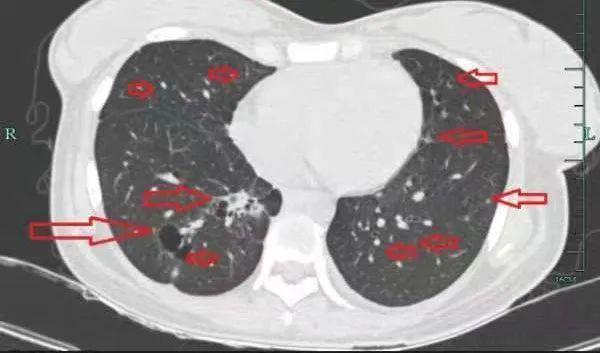

治疗后

几个月后,她的病情逐渐好转,肺部的“满天星”也消失了!小谢满心感激:“是丁主任救了我的命,让我重获新生!”